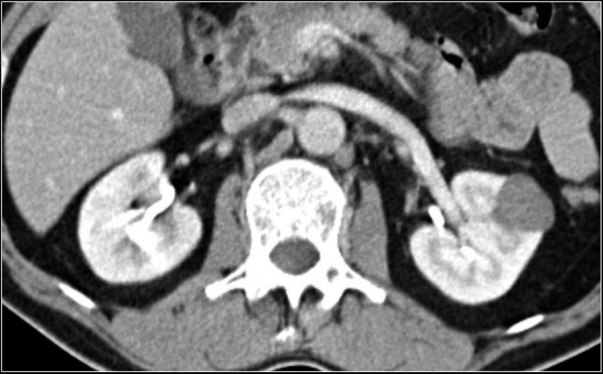

1. Clear cell RCC: These are usually intermediate to high intensity on T2, demonstrate intense heterogeneous enhancement, and may (uncommonly) demonstrate microscopic fat, which is detected on the in-phase and out-phase images. Calcification may be present. The presence of microscopic fat indicates either AML or RCC, but microscopic fat along with calcifications is suggestive of RCC. Although hypervascular, remember that they will still usually appear relatively hypodense compared to the kidneys as the normal kidneys themselves are extremely enhancing. Do not call well enhancing but relatively hypodense renal masses as papillary RCCs!

Classic hypervascular clear cell RCC. Note that the mass still remains hypoattenuating compared to the normal renal parenchyma.

Case courtesy of David Puyó, <a href=”https://radiopaedia.org/”>Radiopaedia.org</a>. From the case <a href=”https://radiopaedia.org/cases/22047″>rID: 22047</a>